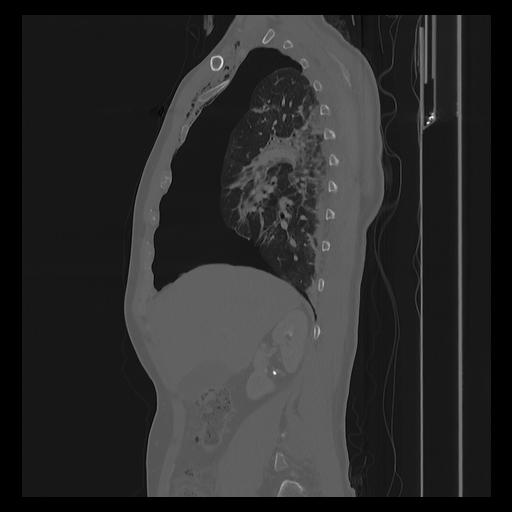

33 PULMON,CE,Sagittal,3.000,PULMON,Sagittal,